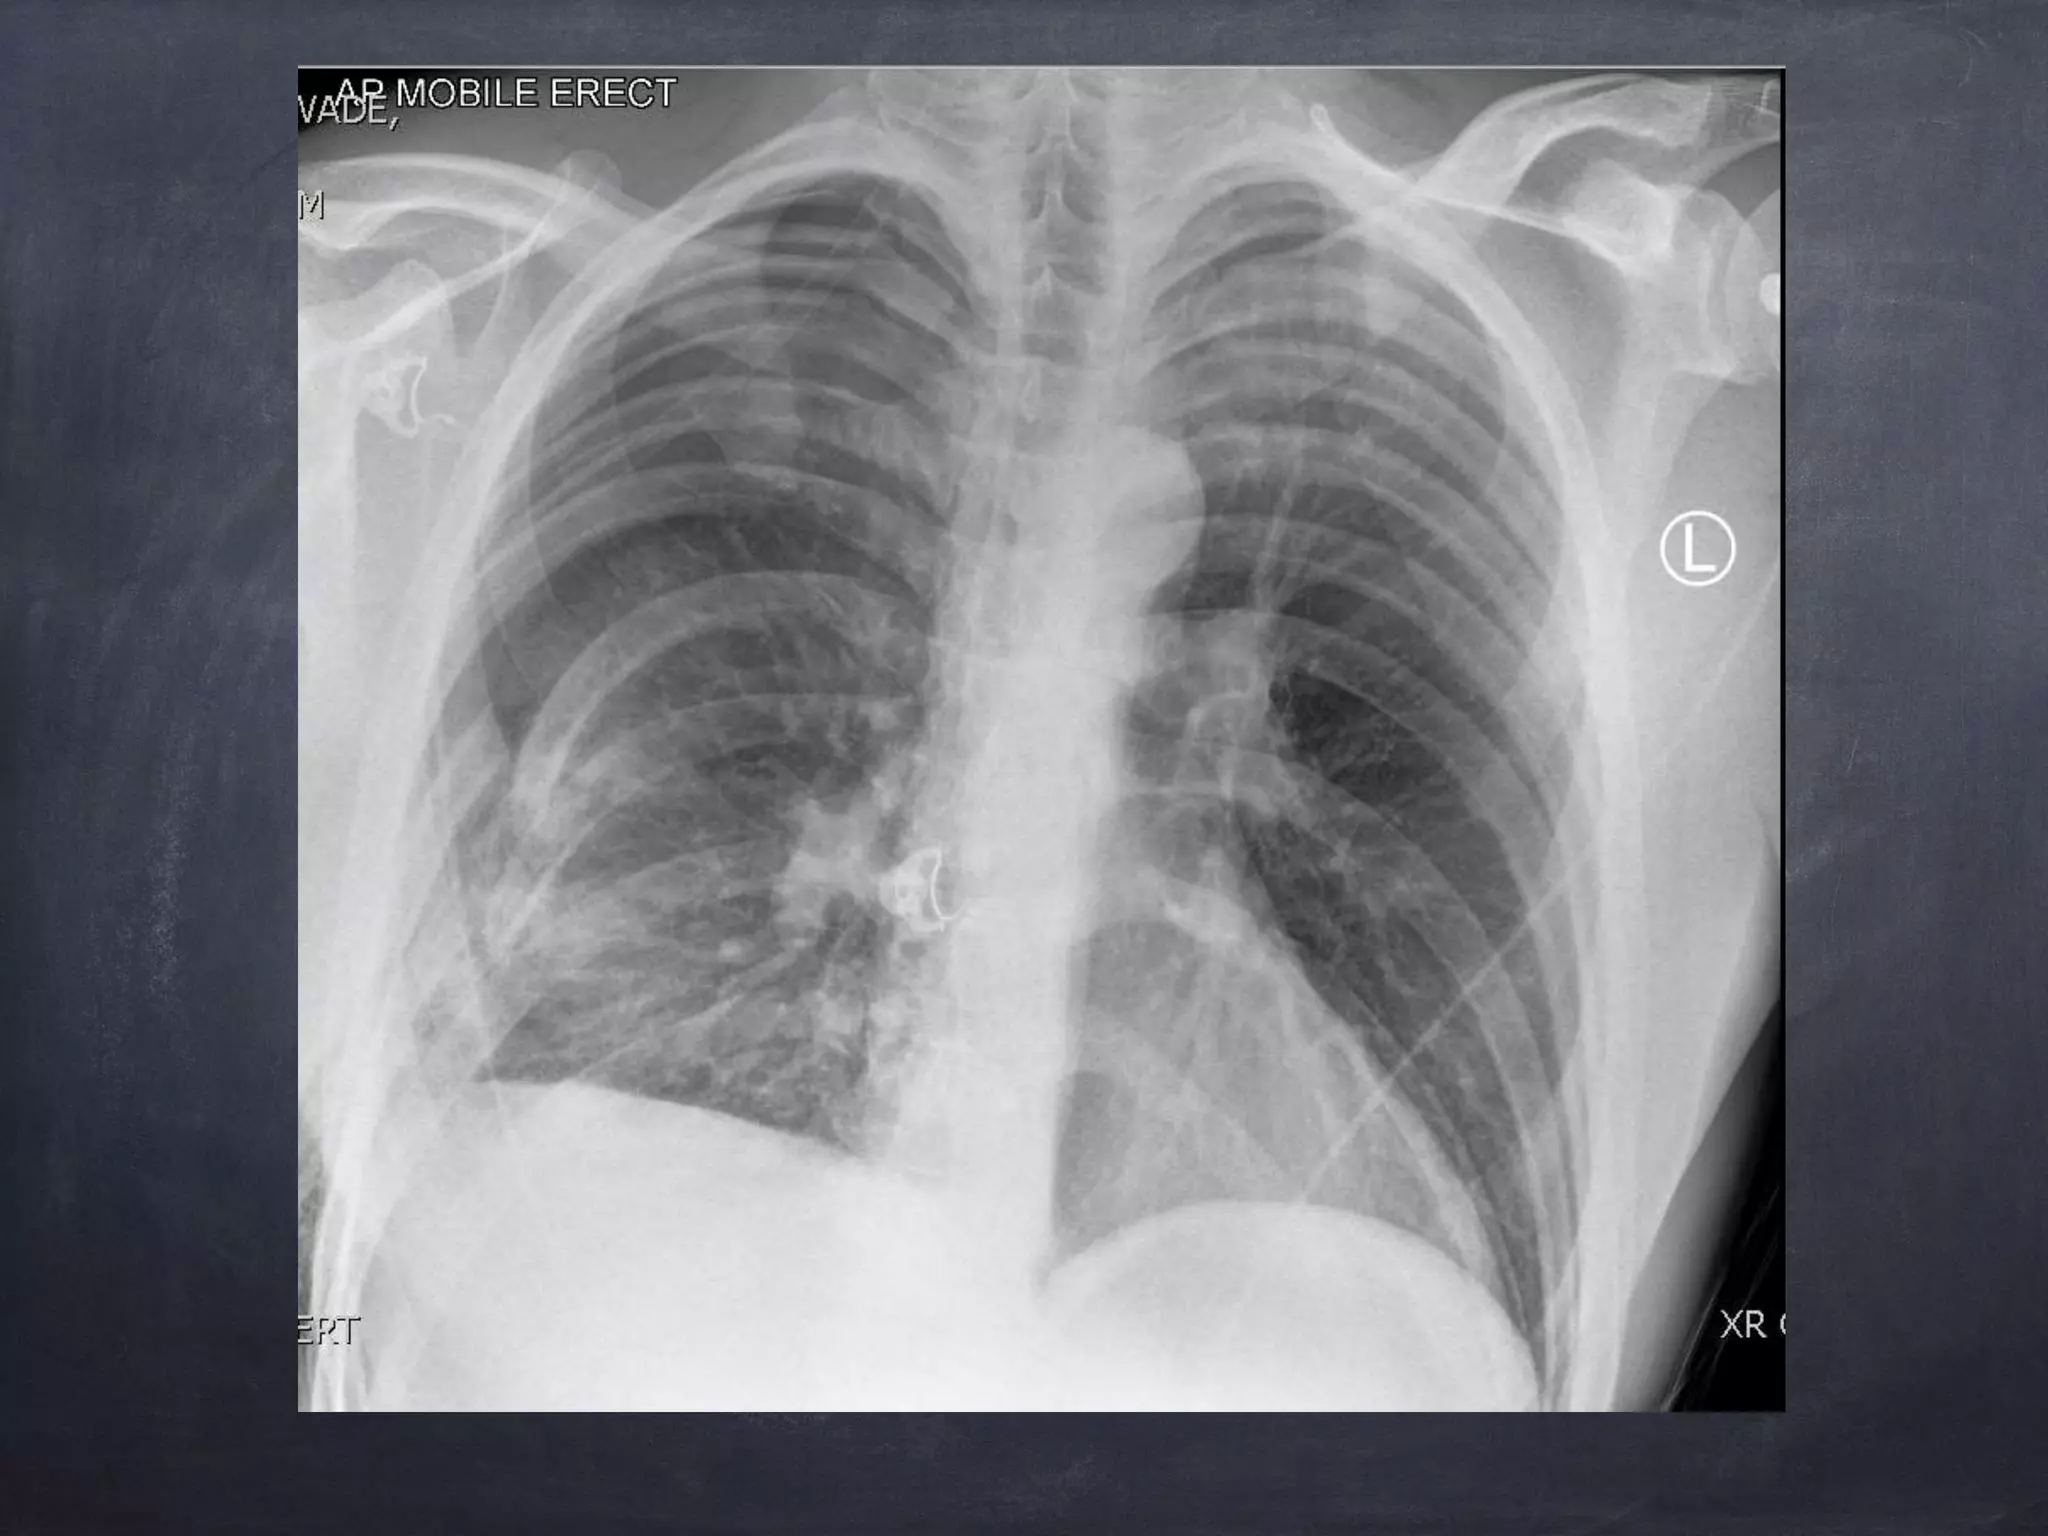

1. The document discusses management of traumatic pneumothoraces, specifically comparing conservative management versus chest drain insertion. Current evidence and guidelines from organizations like BTS and ACCP are limited, with small pneumothoraces under 2cm often managed conservatively with aspiration while larger ones typically require a chest drain. 2. Chest drain insertion involves consideration of needle versus finger thoracotomy and proper tube size, often larger at 26-28Fr or even up to 40Fr for trauma. Cardiothoracic consultation is recommended for any patient with rib fractures to consider procedures like open reduction internal fixation or intercostal nerve blocks. 3. Traumatic pneumothoraces often require larger chest tubes and consultation is